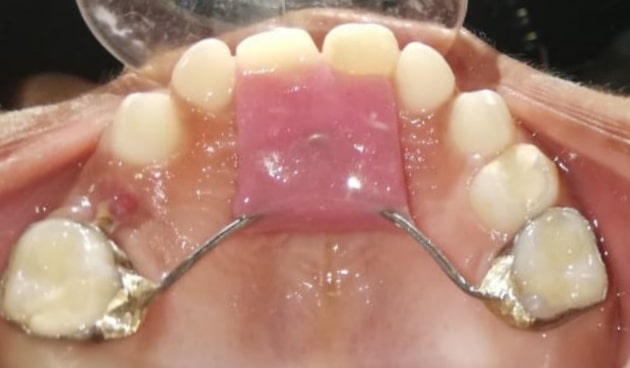

We at the Department of Pediatric & Preventive Dentistry focus on comprehensive oral health care needs of a child from infancy to adulthood and provide comprehensive, therapeutic as well as preventive care to all children including those with special care needs.

- Signed MOU with Government of Maharashtra for the sealant program in Chandrapur District.

Treatment and Services